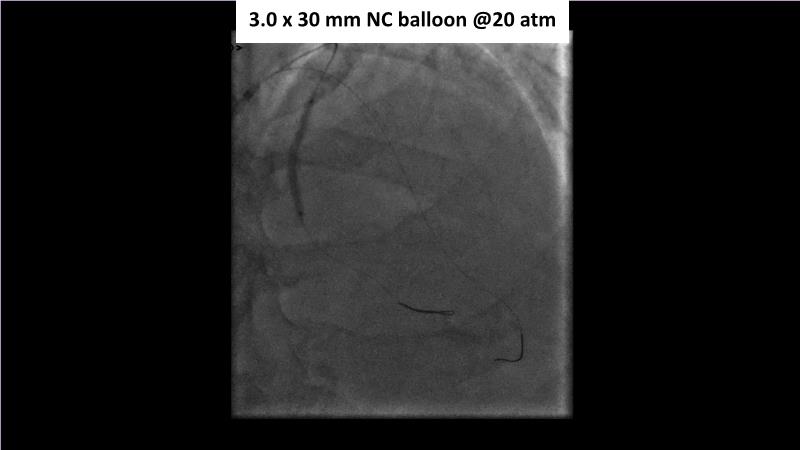

Sirolimus-coated balloon: expanding the scope of indications for complex coronary artery disease treatment

Watch this session to gain case-based insights on using DCBs in complex settings. Learn valuable tips and tricks for optimal DCB application, including the best timing and situations for their use. Discover how to effectively implement a hybrid strategy that combines DES and DCB when needed.

- To learn about tips and tricks on how and when to use a DCB: the ideal time and situation of DCB application in various complexities